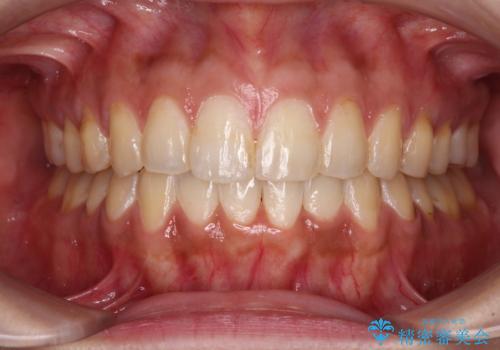

上下前歯の前歯と腫れやすい歯肉 インビザライン矯正で改善